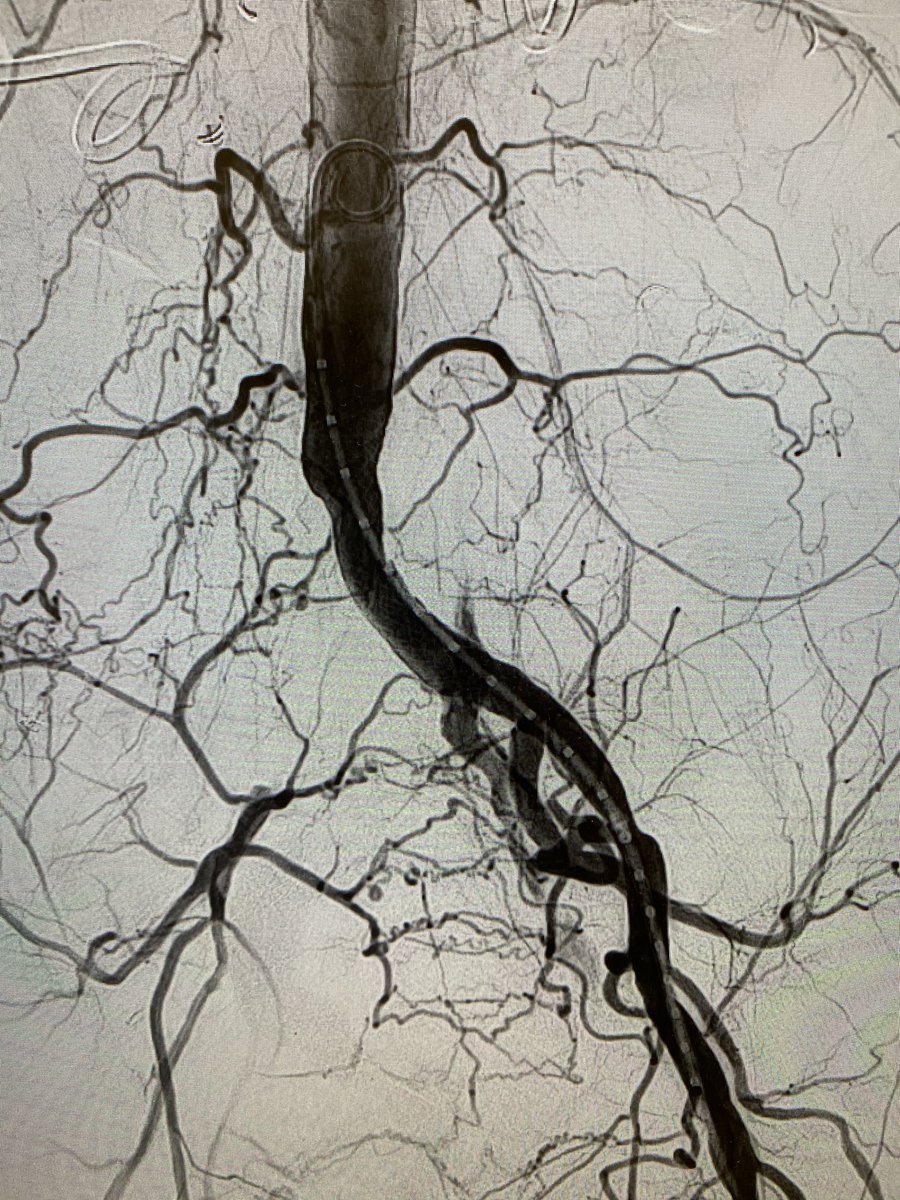

Malignant SVC syndrome w/ stridor; central upper extremity/IJ #DVT; @InariMedical FlowTriever for acute thrombus and ClotTriever for more than expected subacute/chronic; @BDandCo #Venovo for reconstruction @RonaldWinokurMD @TJUHospital @JeffersonRads @kekstero78 @carin_gonsalves